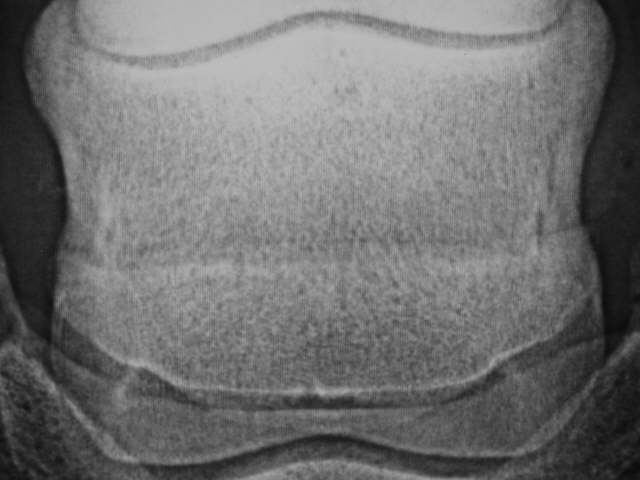

Strahlbein ohne Gefäßkanäle aber etwas vermehrt ausgebildeten seitlichen Bandansätzen (Peaks).